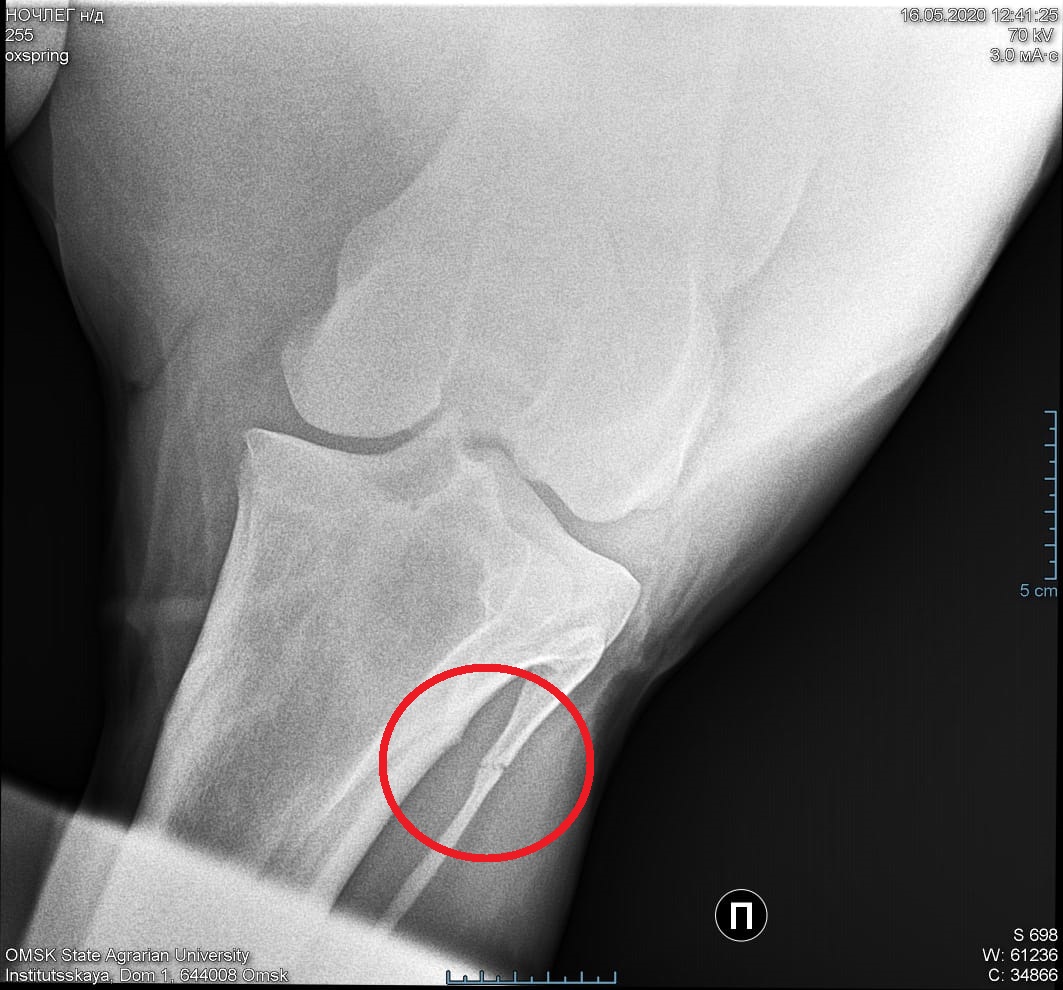

Очень нужна помощь. Конь хромает в течение 4 месяцев на заднюю правую ногу, со временем начал хромать и на левую. Появилась дуга на правой ноге над скакательным суставом. Вся нагрузка приходится на левую ногу, т.к. на правую не опирается, стоит на зацепе, при этом нога подведена под живот и развернута наружу.

Не можем установить причину хромоты. Первое время кололи противовоспалительные препараты, втирали разогревающие мази - улучшений не наблюдается. Делали блокады в скакательный сустав и межкостный мускул.

Провели флекс-тесты - дали положительный результат на колено и скакательный сустав.